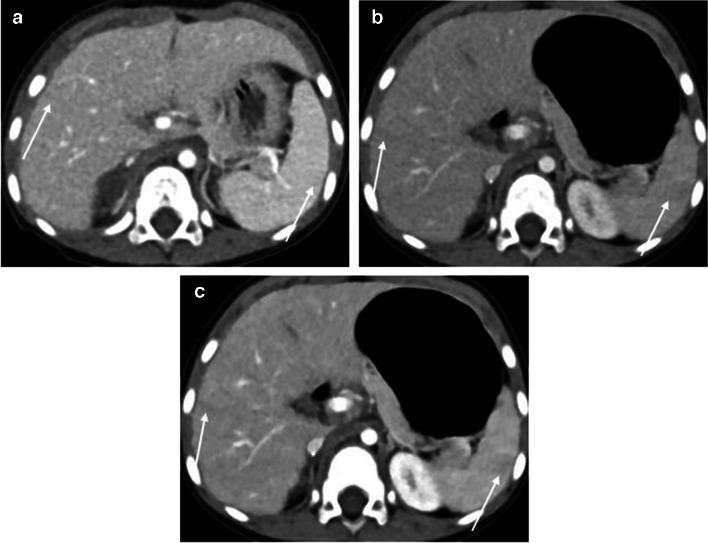

The standard-dose group exhibited higher attenuation, contrast-to-noise ratio (CNR), and signal-to-noise ratio (SNR) of organs and vessels compared to the low-dose group (all P-values < 0.05 except for liver SNR, P = 0.12). However, noise levels did not differ between the standard- and low-dose groups (P = 0.86). The contrast-boosted group had increased attenuation, CNR, and SNR of organs and vessels, and reduced noise compared with the low-dose group (all P < 0.05). The contrast-boosted group showed no differences in attenuation, CNR, and SNR of organs and vessels (all P > 0.05), and lower noise (P = 0.002), than the standard-dose group. In qualitative analysis, the contrast-boosted group did not differ regarding vessel enhancement and lesion conspicuity (P > 0.05) but had lower noise (P < 0.05) and higher organ enhancement and artifacts (all P < 0.05) than the standard-dose group. While iodine uptake was significantly reduced in low-iodine-dose CT (P < 0.001), there was no difference in radiation dose between standard- and low-iodine-dose CT (all P > 0.05).

Low-iodine-dose abdominal CT, combined with an AI-based contrast-boosting technique exhibited comparable organ and vessel enhancement, as well as lesion conspicuity compared to standard-iodine-dose CT in children. Moreover, image noise decreased in the contrast-boosted group, albeit with an increase in artifacts.

结果

与儿童标准碘剂量CT相比,低碘剂量腹部CT联合基于AI的造影剂增强技术在器官和血管强化以及病变清晰度方面表现相当。此外,造影剂增强组的图像噪声降低,尽管伪影有所增加。